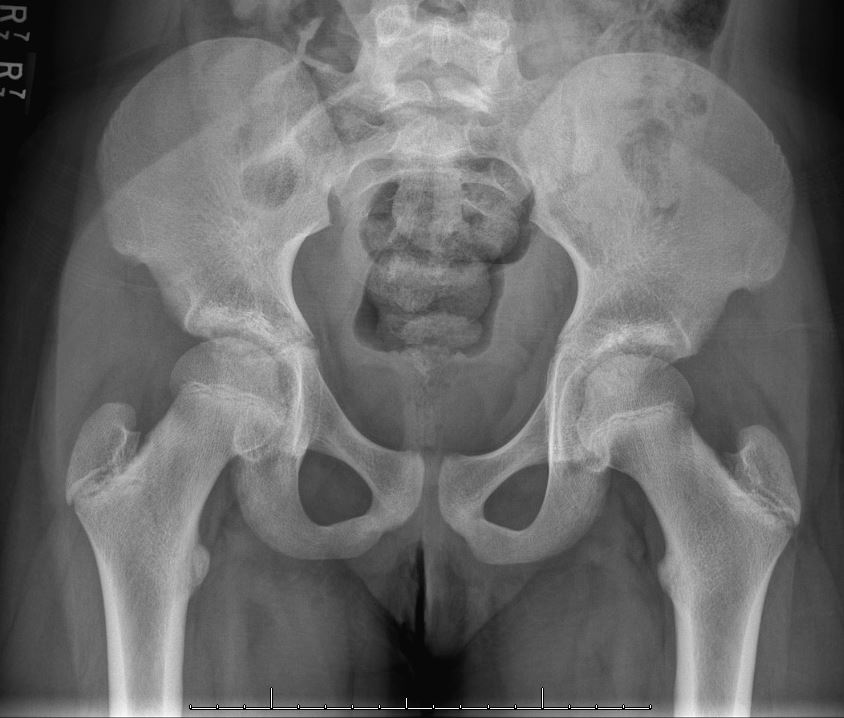

1. 방사선 소견

특별히 이상이 없는 경우가 많습니다. 관절내 염증과 삼출액 증가에 따른 고관절 주위 연부 조직의 음영의 변화 (관절막 팽창) 에 따라 내측 관절 간격이 증가하고, 골두가 외측으로 전이되기도 합니다. 물론 LCP 라고 불리는 병의 초기 소견과 유사하기도 하므로 회복 후 6~8주 후 추적검사가 필요합니다.